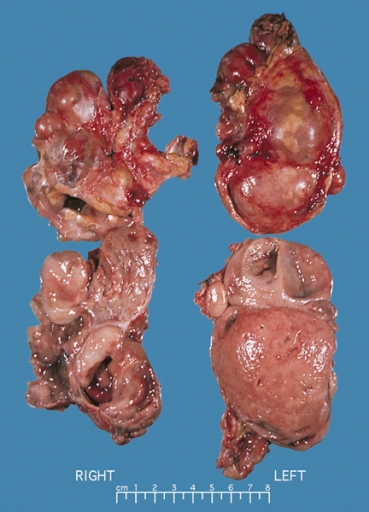

12. Phenochomocytoma picture (http://health-pictures.com/pheochromocytoma.htm); Geneva Foundation of Medical Education and Research, Pheochromocytoma, http://www.gfmer.ch/selected_images_v2/detail_list.php?cat1=1&cat2=113&cat3=22&cat4=2&stype=n .

13. Brown H, Goldberg PA, Selter JG, Cabin HS, Marieb NJ, Udelsman R and Setaro JF Hemorrhagic Pheochromocytoma Associated with Systemic Corticosteroid Therapy and Presenting as Myocardial Infarction with Severe Hypertension. Clinical Case Seminar, J Clin Endocrinol Metab 2005 90: 563-569. (http://jcem.endojournals.org/cgi/content/full/90/1/563).

194. Multiple endocring neoplasia type 2; Bilateral pheochromocytomas associated with multiple endocrine neoplasia type 2 http://en.wikipedia.org/wiki/Multiple_endocrine_neoplasia_type_2 ; http://en.wikipedia.org/wiki/File:Bilateral_pheo_MEN2.jpg . public domain image.

195. Pheochromocytoma, public domain, http://en.wikipedia.org/wiki/File:Pheochromocytoma.jpg . (Choyke PL Glenn  GM Walther W Patronas NJ Linehan WM Zbar B, Radiology (March) 146: 629-642, 1995, http://www.cc.nih.gov/ccc/papers/vonhip/adrenal.html .)

196. Fitzgerald PA Adrenal Medulla & Paraganglia (Chapter 12) in Greenspan's Basic & Clinical Endocrinology, 8th edition, Gardner DB and Shoback D, eds, on-line edition, The McGraw-Hill Companies, 2007.